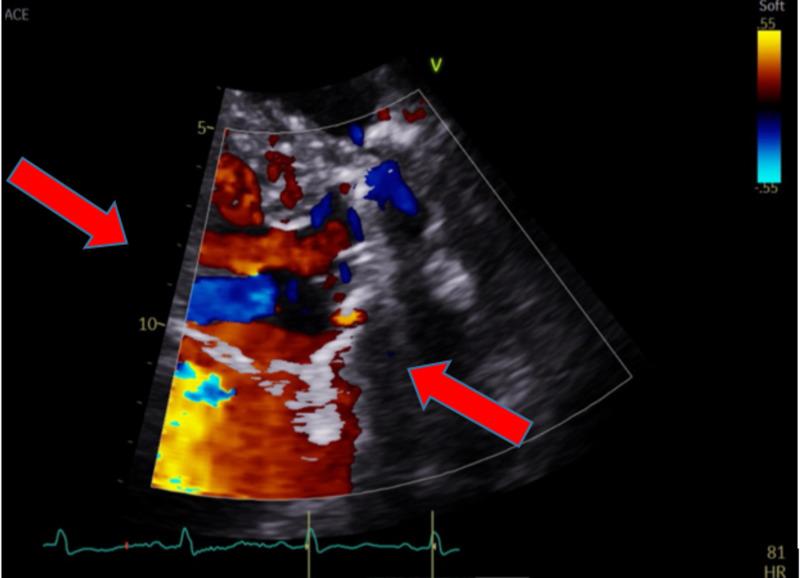

二尖瓣置换术后瓣周漏的复杂病例

A Complicated Case of a Paravalvular Leak Following Mitral Valve Replacement.

Paravalvular leaks (PVL) are an uncommon sequelae of valve replacement but can be seen as a complication of both mechanic and prosthetic valves. Patients with PVL may remain asymptomatic or have detrimental complications, which include heart failure, hemodynamically significant hemolysis, and endocarditis. Management depends on the clinical presentation and the degree of the valvular leak. We hereby present a case report of a patient with a complicated clinical course secondary to a PVL of the mitral valve. The patient had a recent mitral valve replacement and presented with symptoms of heart failure that was refractory to standard medical therapy. Valvular abnormality was not seen with initial trans-thoracic echocardiogram (TTE), but with high clinical suspicion, a trans-esophageal echocardiogram (TEE) was done confirming a PVL. The patient's condition continued to deteriorate; he became hemodynamically unstable with end-organ damage. Cardiothoracic surgery was consulted for surgical repair of the PVL. The patient, however, remained too unstable for surgery and the family opted for comfort measures per the patient's wishes.

摘要

瓣周漏(PVL)是瓣膜置换术后不常见的后遗症,但可视为机械瓣膜和人工瓣膜的并发症。瓣周漏患者可能无症状或出现有害并发症,包括心力衰竭、具有血流动力学意义的溶血和心内膜炎。治疗取决于临床表现和瓣膜漏的程度。我们在此报告一例二尖瓣瓣周漏继发复杂临床过程的病例。该患者近期进行了二尖瓣置换术,出现了标准药物治疗无效的心力衰竭症状。最初的经胸超声心动图(TTE)未发现瓣膜异常,但由于临床高度怀疑,进行了经食管超声心动图(TEE)检查,证实存在瓣周漏。患者病情持续恶化;他出现血流动力学不稳定并伴有终末器官损害。咨询心胸外科进行瓣周漏的手术修复。然而,患者仍因过于不稳定而无法进行手术,家属根据患者意愿选择了姑息治疗措施。